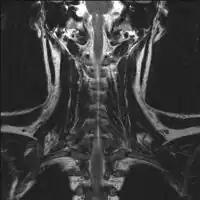

1.b. CT scan: solitary plasmacytoma upper arm near shoulder 2.a. MRI neck (side view): solitary plasmacytoma C6

2.a. MRI neck (side view): solitary plasmacytoma C6 2.b. MRI neck (view from behind): solitary plasmacytoma C6

2.b. MRI neck (view from behind): solitary plasmacytoma C6